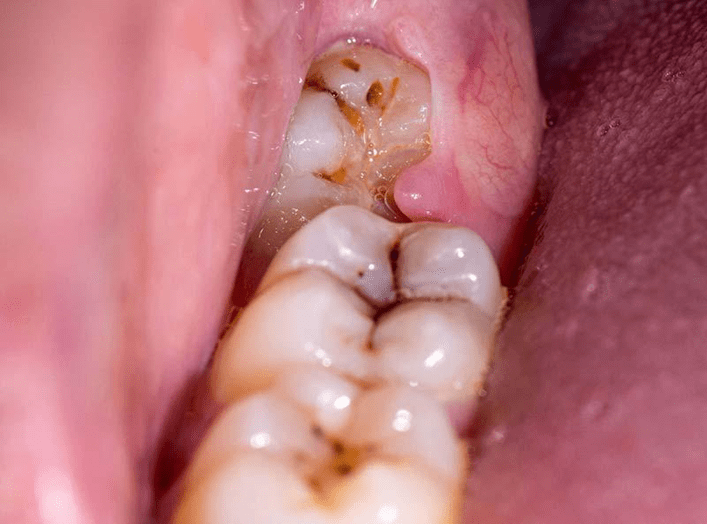

1. Consultation and X-Ray

The dentist evaluates the position of the tooth.

What Is an Impacted Wisdom Tooth?

An impacted wisdom tooth occurs when the tooth does not fully emerge from the gums due to lack of space.

Types of impaction include:

- Horizontal impaction

- Vertical impaction

- Partial eruption

- Fully impacted tooth

Impacted teeth can cause infection, pain, and damage to nearby teeth.